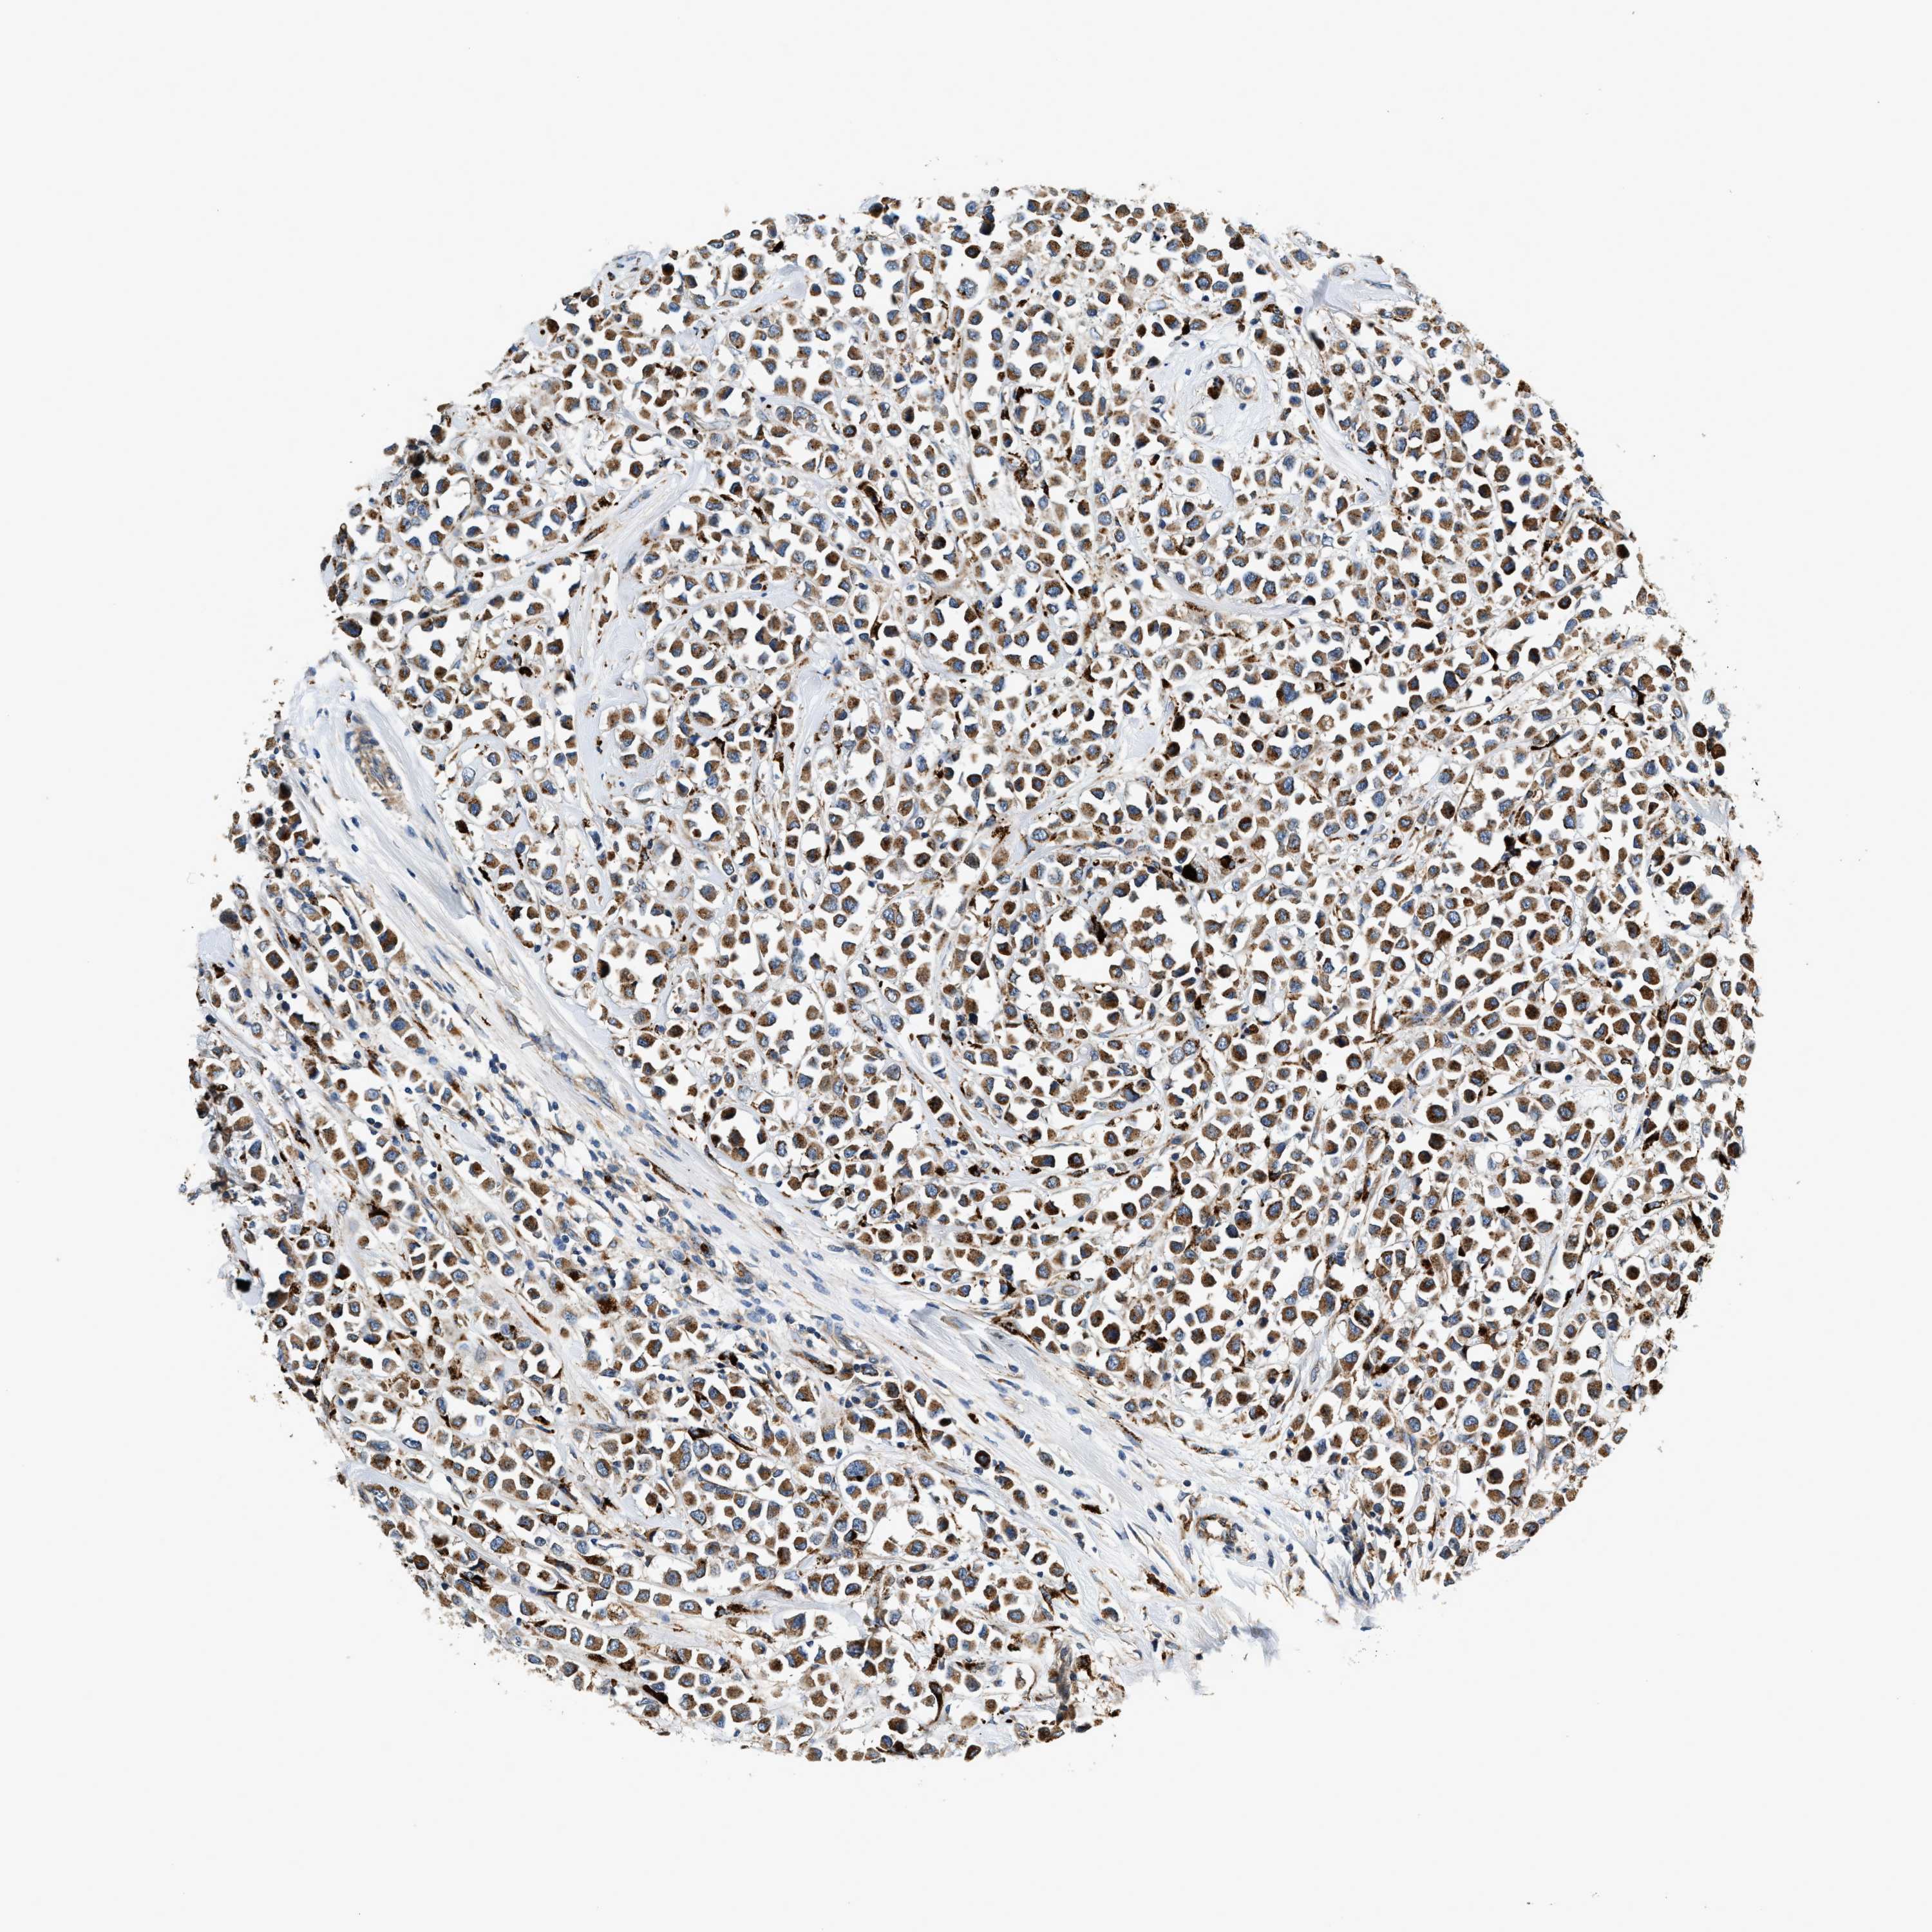

CANCER BREAST CANCER Show tissue menu

BRCA TCGA BRCA VALIDATION PROTEIN EXPRESSION